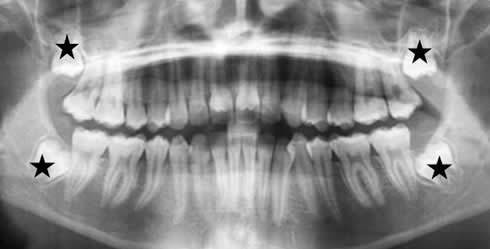

Fig 3. Dentición permanente.

Fig 4. Dientes normales.

Los últimos molares (Piezas 8 de los 4 cuadrantes), aún no están erupcionados.

Esto es normal en los adolescentes y adultos jóvenes.